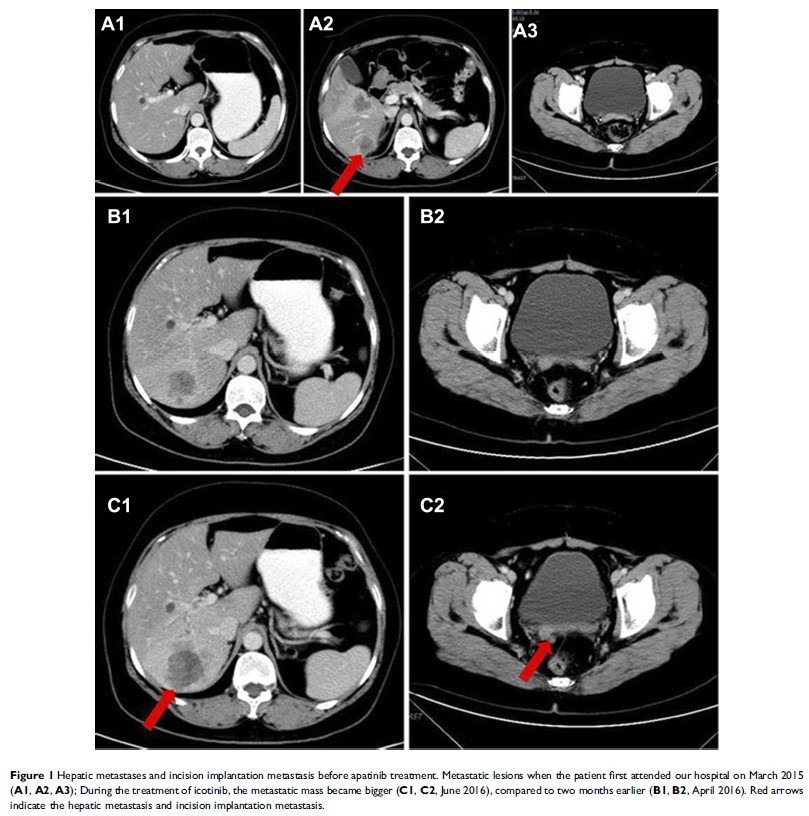

Case Report

- 作者:Di Zhang, Jiaqi Huang, Yulan Sun, Qisen Guo

- 期刊:OncoTargets and Therapy